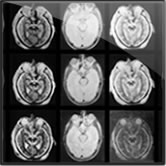

Horizontal Atlas

Coronal Atlas

Sagittal Atlas